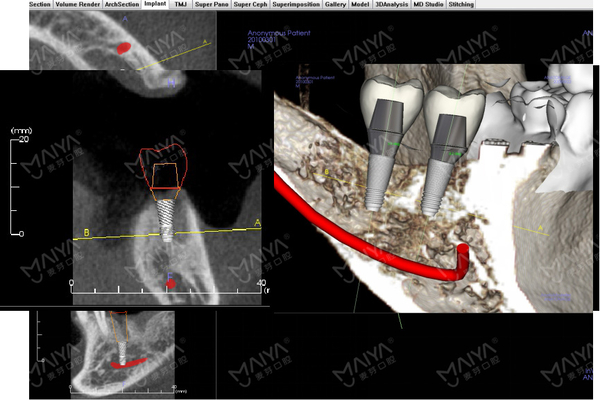

无牙颌口腔种植技巧为种植修复领域的难题,涉及种植牙位置设计、咬合关系重建、植入角度控制、支持方式与附着体的选择、及种植术前评估与风险多方面,稍有差池都有可能失败。

为提升广大医师无牙颌种植领域实战技能与临床应用水平,6月26日~6月27日,会议将以无牙颌口腔种植领域研究课题为核心内容,围绕无牙颌种植术前检查与评估,方案设计,无牙颌外科手术原则,无牙颌模型外科植入,无牙颌种植修复种类和设计原则,无牙颌修复材料选择、咬合设计和维护,无牙颌种植修复流程,无牙颌种植治疗中的并发症处理及维护等十余项课题展开详细的课题研讨与,6月28日进行无牙颌案例手术直播演绎,目前,本届探讨会议已吸引广州、深圳数十名牙医报名。